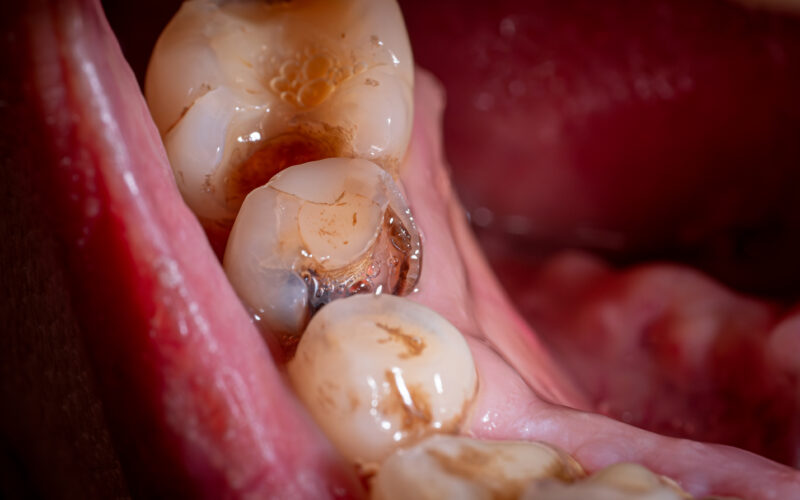

Stage 3: Decay reaching dentin

Once decay penetrates the enamel and reaches the dentin layer underneath, it typically spreads more rapidly because dentin is softer and less mineralized. Sensitivity to sweets, cold, or biting pressure may start at this stage. At this point, the cavity usually requires a filling, and delaying treatment allows it to grow faster. This progression from enamel to dentin can occur over months, especially if risk factors are not addressed.